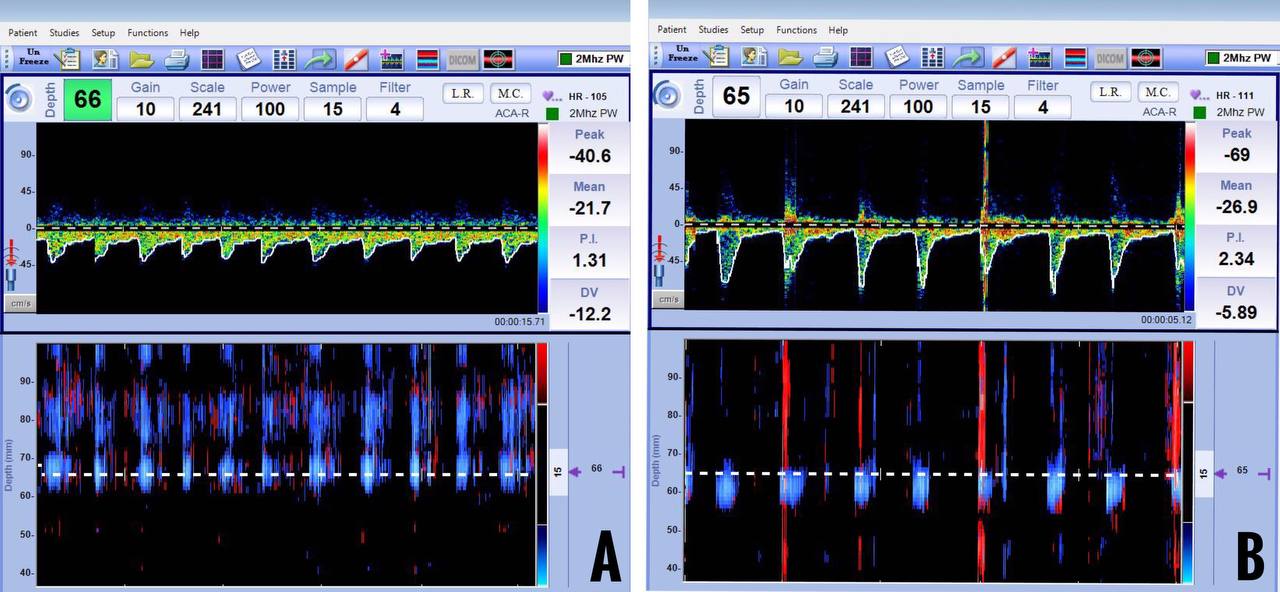

Velocity criteria for vasospasm in MCA have been well established. An MFV of more than 120 cm/sec suggests vasospasm in the clinical context of aneurysmal SAH. Severe vasospasm is suspected when MFV is more than 200 cm/sec. Sometimes, only a gradual increase in flow velocities per day (more than 50 cm/sec) is observed in the first few days after aneurysmal rupture. One important differential diagnosis for increased velocities is hyperemia. It is important to look at velocities in extracranial circulation to differentiate vasospasm and hyperemia reliably. The LR has been developed specifically for this purpose. A MFV of more than 120 cm/sec and a LR of more than 3 indicate vasospasm (Figure 13).

Figure 13: Elevated mean flow velocities in the middle cerebral artery (A) and normal mean flow velocities in the extracranial internal carotid artery (B). The calculated Lindegaard Ratio is 4.6 and suggestive of mild-moderate vasospasm.